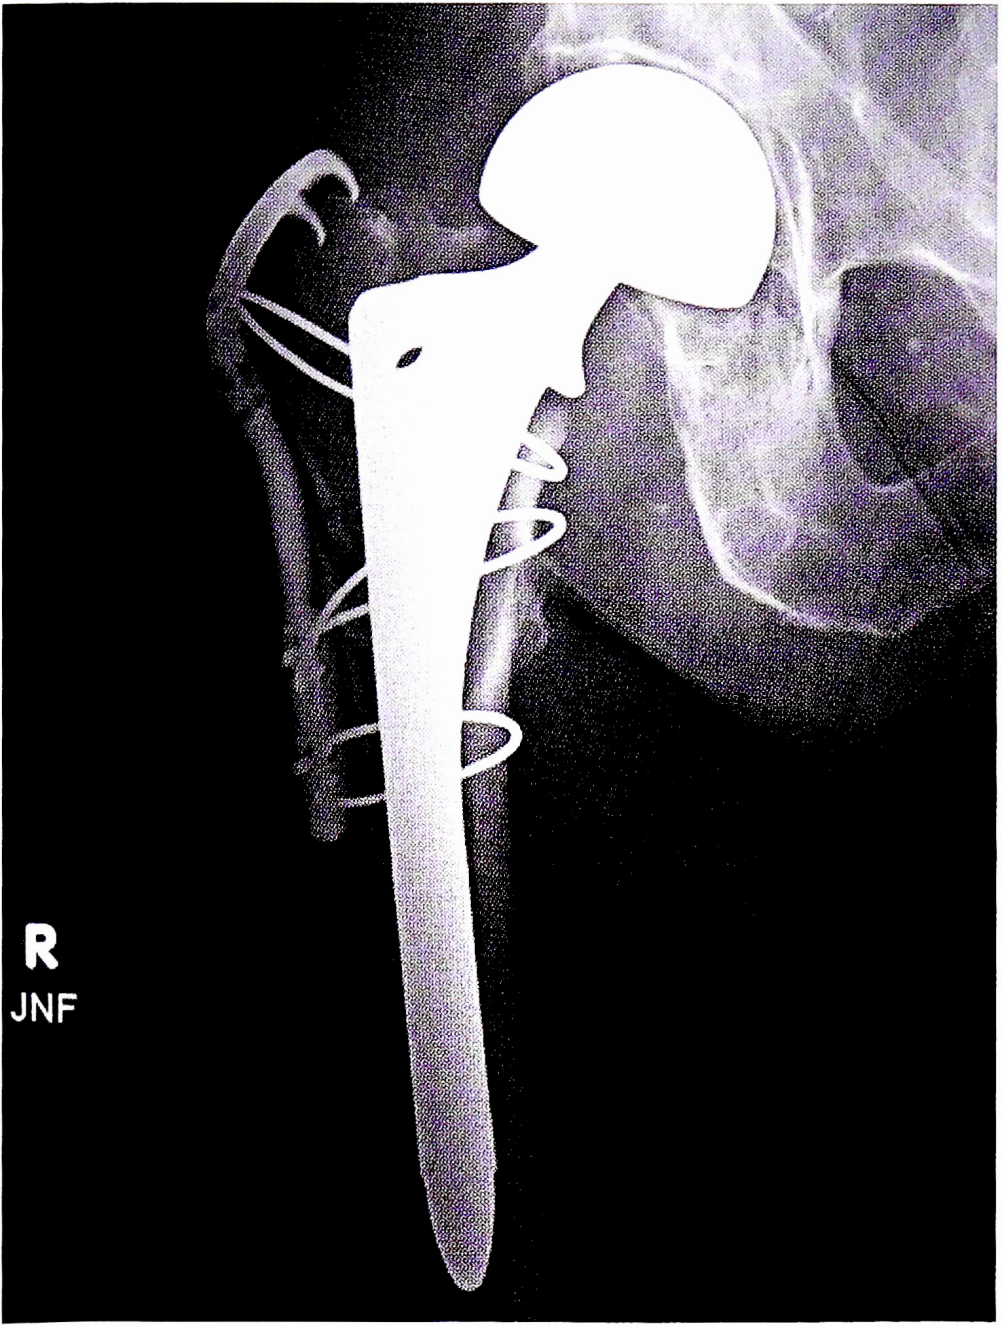

Методы устранения перипротезных переломов усложняются от подтипа к подтипу. Так, достаточным объемом лечения переломов типа А1 (точечные перфорации в проксимальном отделе БК) является импактирование перфораций костной стружкой, полученной при обработке вертлужной впадины. Предпочтительным методом лечения переломов типа А2 (стабильные линейные переломы проксимального отдела БК) является наложение проволочных серкляжей до имплантации ножки для предотвращения распространения линии перелома. Для лечения переломов типа АЗ (нестабильные переломы проксимального отдела БК) можно использовать полнопокрытые или конические с ребристой поверхностью ножки, что обусловлено базовыми биомеханическими принципами. Большой вертел (в случае его отрыва) допустимо фиксировать при помощи серкляжной проволоки, путем остеосинтеза спицами по Веберу (рис. 3) или специальными вертельными пластинами (рис. 4,5) [34].

Рис. 3. Интраоперационный перипротезный перелом большого вертела типа АЗ. Остеосинтез спицами по Веберу. Большой вертел стабилен.

Fig. 3. Intraoperative periprosthetic greater trochanter fracture ТуреА3. Osteosynthesis with pins by Weber. The greater trochanter is stable.